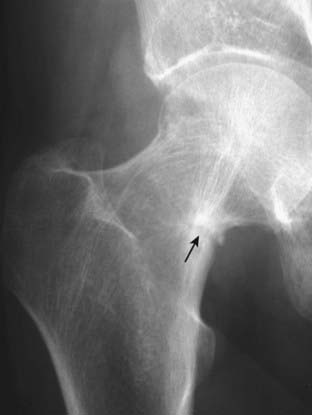

image

Figure 21-9 Avascular necrosis of the left femoral head in a patient on long-term steroids for lupus erythematosus.

A close-up view of the left femoral head shows a zone of increased sclerosis in the superior aspect of the femoral head (solid white arrows), a characteristic finding of avascular necrosis of the head. The linear, subcortical lucency (solid black arrow) represents subchondral fractures seen with this disease, called the crescent sign. Notice that the disease is isolated to the femoral head and involves neither the joint space nor the acetabulum, i.e., this it is not an arthritis.